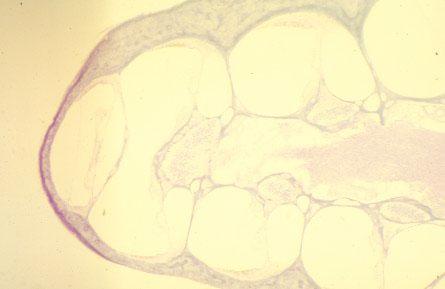

X-36 (3) Slide 84, Rodent Ear (H&E). Cochlea. Observe cochlear nerve (right) and helicotrema (far left). Modiolus is the middle spiral axis of bone.